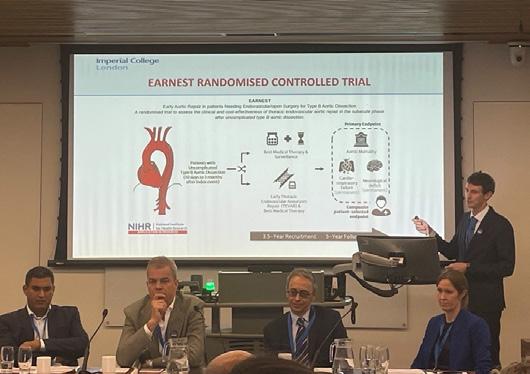

The UK National Institute of Health Research (NIHR)-funded EARNEST randomised controlled trial aims to recruit the first patients from March 2025, Colin Bicknell (Imperial College London, London, UK) tells Vascular News

Bicknell, pictured here at IADS, explains that EARNEST will address the question of whether thoracic endovascular aortic repair (TEVAR) in the subacute phase after uncomplicated type B aortic dissection (TBAD) in addition to best medical therapy (BMT) compared to BMT and surveillance confers a long-term advantage and whether this practice is cost effective. He notes that 470 patients with uncomplicated TBAD will be recruited in vascular centres throughout the UK.

“The results are expected to inform international guidelines and change practice in the UK and abroad,” Bicknell comments.

In addition, Bell noted ongoing problems with image transfer and safe interhospital transfer. Here, the presenter referenced notable regional disparities. “As you get higher and higher up the country, there’s less support for appropriate interhospital transfer,” she said, specifying that in the North East the interhospital transfer is not provided 24/7. Finally, Bell highlighted future opportunities around research. She mentioned in particular the UK-specific EARNEST trial, which is set to commence recruitment in March 2025. The study, Bell explained, “hopefully will answer some questions about what we do with those patients who are initially treated medically but we think may benefit from endovascular intervention in the subacute phase, and whether that will make a difference to their longer-term mortality.”